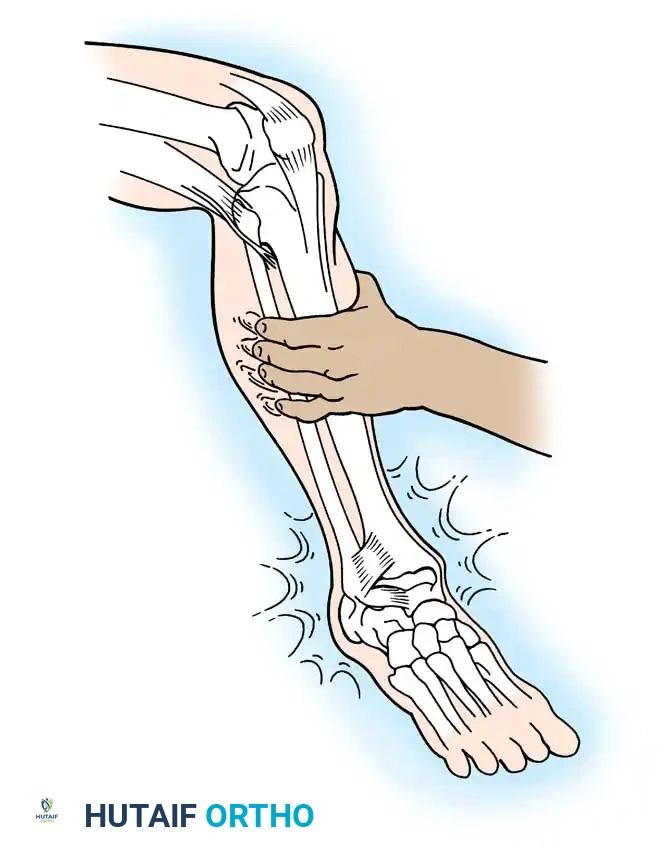

Clinically, the maneuver is performed by placing the tip of the thumb on the anterior aspect of the lateral malleolus while palpating the lateral talar process with the base of the thumb. With gentle anterior stress applied to the heel while stabilizing the tibia, the surgeon assesses the degree of anterior translation of the talus relative to the tibial plafond.

Tohyama et al., in a rigorous cadaveric study, demonstrated that applying 30 N of force during the anteroposterior stress test produced a more reliable injured-to-normal displacement ratio than applying 60 N of force. They recommended utilizing a relatively low-magnitude load when evaluating ATFL integrity to prevent secondary restraints from masking the laxity.

Anderson and LeCocq stated that 3 mm of forward talar displacement on stress radiographs is pathological and indicates lateral ligamentous rupture. However, the clinical sensation of the talus subluxating out of the mortise (the "suction sign") is often more diagnostically valuable than absolute millimeter measurements.